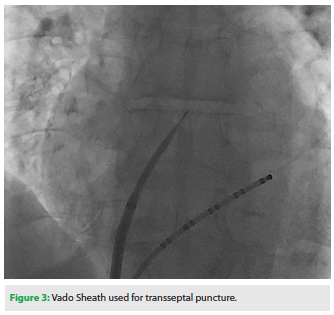

We believe the Vado Sheath significantly improved ablation catheter manipulation and our ability to target veins in the left atrium. Catheter stability was also improved when using the Vado Sheath as compared to the ablation catheter alone. The sheath had excellent visibility under fluoroscopy due to an enhanced dilator radiopacity (Figure 3). Engagement of the fossa ovalis and transseptal puncture using the Vado Sheath was easy to perform and was facilitated by the variable curve. Ablation and Lasso catheters were easily positioned in the left atrium (Figure 4). We found excellent torque transmission when using the Vado Sheath, and no abrupt catheter movements were observed.